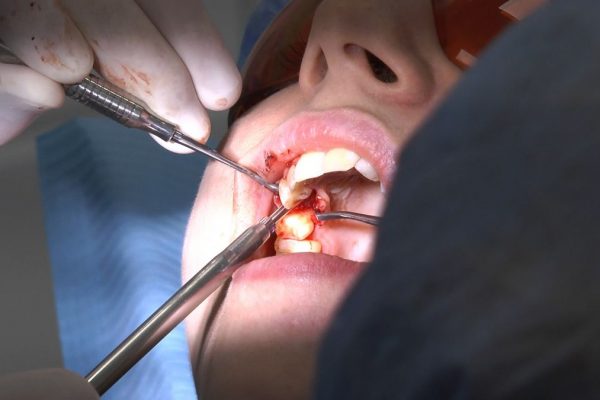

W ostatni weekend czerwca 2018 roku kursanci II Sezonu Preludium Implantologii odbyli piątą, finałową sesję, która w całości podporządkowana była praktyce. W ciągu dwóch dni zabiegowych Lekarze uczestniczący w szkoleniu przeprowadzili szereg zabiegów pod kierunkiem dr n.med. Violetty Szycik. Wszczepili 17 implantów oraz przeprowadzili ekstrakcje i zabiegi regeneracyjne kości. Zabiegi były wykonywane także w sedacji dożylnej z udziałem specjalisty anestezjologii i intensywnej terapii dr Jolanty Grzybowskiej. Preludium implantologii to nowy program edukacyjny dla adeptów implantologii stomatologicznej, którego celem jest wprowadzenie do implantologii poprzez pozyskanie wiedzy w szerokim zakresie i uwzględnieniem szczegółów mających decydujące znaczenie dla powodzenia leczenia implantologicznego. Ale tak jak wszystkie szkolenia w Instytucie Vivadental, w tym wiodące Practiculum Implantologii, zorientowane jest na praktyce i samodzielnym wykonywaniu zabiegów pod kierunkiem Mentora. To najlepsza edukacja w medycynie zabiegowej, a zarazem najlepszy start do implantologii.